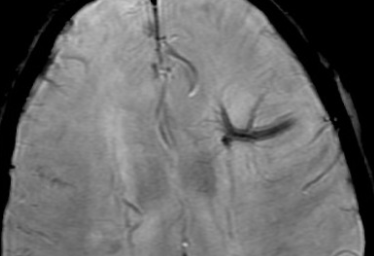

- Aspect en tete de méduse (ne pas confondre avec nidus de la MAV Cérébrale)

Venous developement developpement anomaly